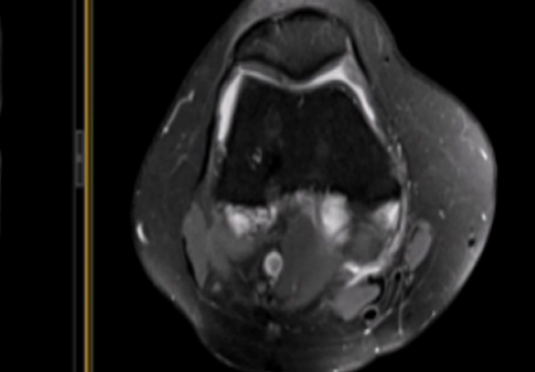

微創(chuàng)射頻消融術(shù)

適用于微創(chuàng)射頻熱消融術(shù)治療患者,引進權(quán)威醫(yī)療團體輔助引流。